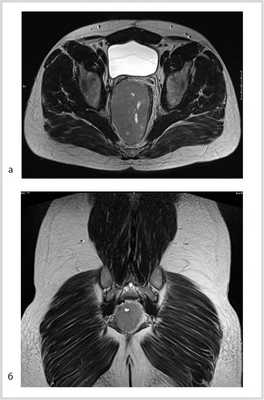

Рис. 3. МР-томограммы малого таза. Опухоль уменьшилась в размере до 5,5×3,5×4 см, однако тесно прилежит к правой стенке прямой кишки. а — аксиальный срез; б — сагиттальный срез; в — фронтальный срез.